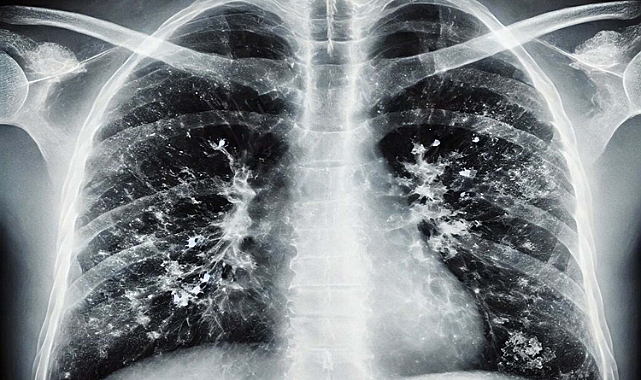

'Kışın solunum yolu enfeksiyonlarında artış doğal, hijyen şart'

İzmir'de İl Sağlık Müdürlüğü Halk Sağlığı Hizmetleri Başkanlığı Başkan Yardımcısı Doktor Metin Kızılelma, kış aylarında solunum yolu enfeksiyonlarında artışın doğal ve bu enfeksiyonlardan korunmanın en önemli etkenin ise 'hijyen' olduğunu söyledi.